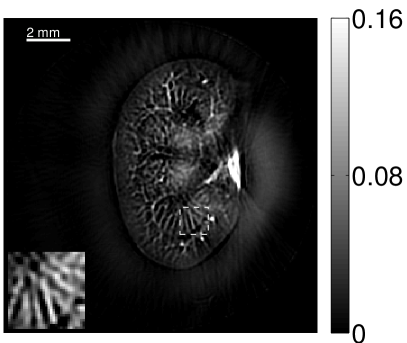

The images and EIRs reconstructed by use of the VP algorithm that was based on the 2D imaging model that neglected the SIR are shown in Figures 15 and 16. The latter figure contains results corresponding to different values for the regularization parameter . From Fig. 15, it can be observed that use of the conventional iterative method that utilized the measured EIR resulted in distortions and loss of details in the reconstructed images. Use of the VP algorithm improved the contrast and the details in the reconstructed images (Fig. 15(c) and 16(a)). Furthermore, the images reconstructed by use of the VP algorithm had a more uniform background.

In Figure 17, the results corresponding to use of the 3D imaging model that incorporated SIR effects are shown. The EIR estimated by the VP algorithm is also shown. In Figure 18, images and EIRs reconstructed by use of the VP algorithm with different regularization parameters values are shown.

Similar to the case described above where the transducer SIR was neglected, these results reveal that use of the VP algorithm can produce images with a cleaner background and enhanced spatial resolution than yielded by use of a conventional iterative algorithm that employed the measured EIR. For example, detailed information regarding the vessels near the organ’s periphery was better preserved by the VP algorithm than by the conventional iterative algorithm. These images corroborate our assertion that the VP algorithm can significantly reduce the artifacts and distortions in the reconstructed image. It is also worth pointing out that, unlike the numerical phantom studies, the artifacts and distortions in the images may be caused not only by the inaccurate EIR but also by other factors, such as neglecting acoustic heterogeneities and the variation of the EIRs among the elements of the transducer array. In such cases, the EIR estimated by the VP algorithm represents an effective system impulse response that minimizes the inconsistency between the measured data and the imaging model.